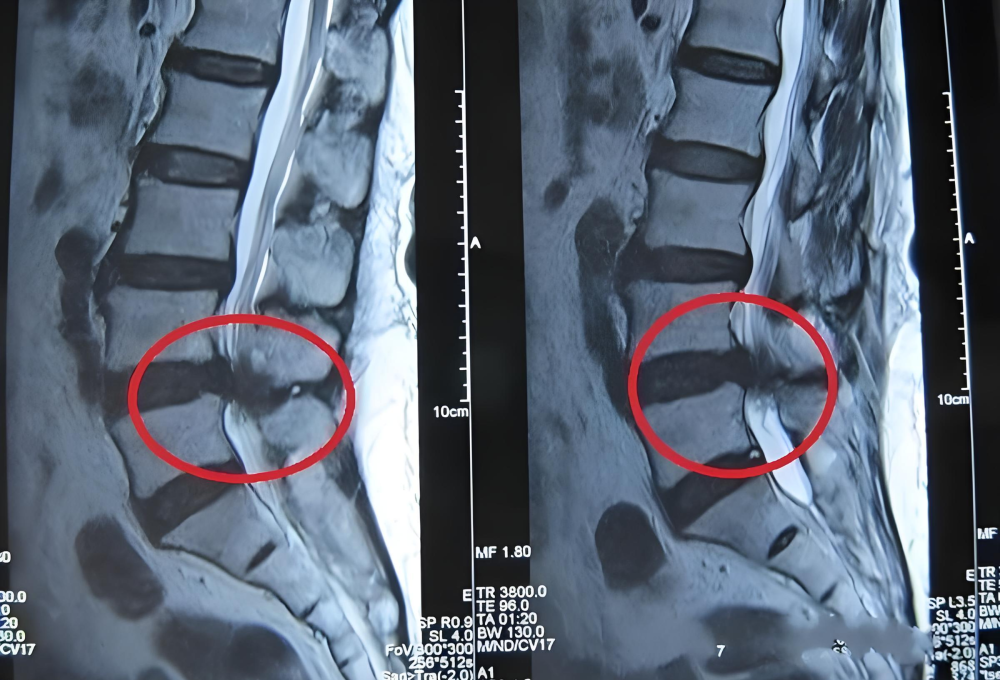

首先,我们要清楚,腰椎间盘突出是椎间盘外侧的纤维环破裂,导致内部的髓核组织向后方突出,进入椎管空间的现象。

图片

单纯的突出未必会产生症状。只有当突出的部分挤压或刺激到神经根,并且神经根受到的压力较大、没有足够空间躲避时,才会出现疼痛、麻木等神经症状。所以本质上,腰椎间盘突出症是一种神经受压迫引发的综合征,其典型症状往往体现在下肢。